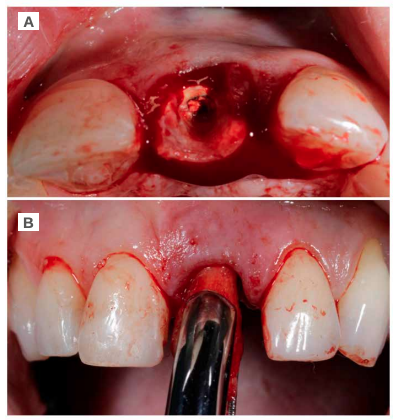

Caso clínico: Se presenta el caso de una paciente mujer de 32 años de edad, que acude por presentar una posible fractura radicular del incisivo central superior izquierdo (ICSI), acompañada de la aparición de un absceso periodontal en la región del fondo de vestíbulo de dicho diente. Tras llevar a cabo la exploración clínica y radiológica, se establece que el pronóstico del ICSI es desfavorable para llevar a cabo un tratamiento conservador del mismo. Tras la valoración de las características clínicas del caso presente, el plan de tratamiento se inclinó por la realización de la exodoncia del ICSI con la colocación simultánea de un IOI postextracción y la carga inmediata con una prótesis provisional del mismo.

Clinical case: We present the case of a 32-year-old female patient who presented with a possible root fracture of the upper left central incisor (ULCI), accompanied by the appearance of a periodontal abscess in the region of the bottom of the vestibule of said tooth. After carrying out the clinical and radiological examination, it is established that the ULCI prognosis is unfavourable for carrying out conservative treatment of the tooth. After assessing the clinical characteristics of the present case, the chosen treatment plan was to extract the ULCI with the simultaneous placement of a post-extraction osseointegrated implant (OII) and immediate loading of a provisional prosthesis on the implant.

Los beneficios de la carga inmediata incluyen una reducción notable de las intervenciones quirúrgicas, una menor dilatación temporal del tratamiento e incluso un mejor bienestar psicológico y social para el paciente. En casos con importante compromiso estético, la carga inmediata o la provisionalización inmediata, añadida a la colocación inmediata postextracción del IOI permiten minimizar las alteraciones derivadas de la pérdida dental, manteniendo el perfil de emergencia, contorno de tejidos blandos y las papilas gingivales5-7.

Así mismo, se han establecido diferentes protocolos para el manejo del sector estético anterosuperior, que se suman al acto de la colocación inmediata del implante y la corona provisional, donde se incluyen la colocación de un material no reabsorbible entre el IOI y la cortical vestibular para minimizar el posible colapso, así como el manejo de los tejidos blandos periimplantarios8-11.